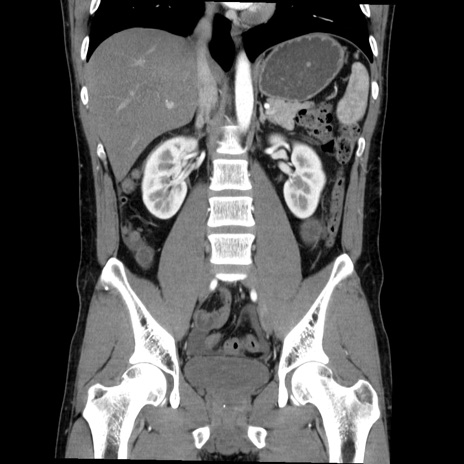

症例36(冠状断像)

【症例】20歳代 男性

【主訴】心窩部痛

【現病歴】今朝より上腹部痛あり。一旦軽快していたが再度出現したため救急要請。昨日夕に白身の魚を含む刺身を食べた。

【身体所見】BP 136/89mmHg、HR 74/min、BT 37.0℃、腹部:膨満、軟、心窩部に圧痛あり。反跳痛なし、筋性防御なし、腸雑音やや亢進あり。

【データ】WBC 17700、CRP 0.48